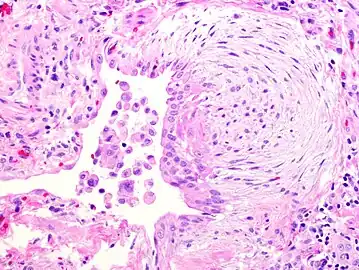

The histologic hallmarks of UIP, as seen in lung tissue under a microscope by a pathologist, are interstitial fibrosis in a "patchwork pattern", honeycomb change and fibroblast foci (see images below).[6] [7]

A fibroblast focus in a surgical lung biopsy of UIP. Hematoxylin-eosin stain, high magnification. The white space to the left is an airspace. The pale area to the right is a fibroblast focus. It is an area of active fibroblast proliferation within the interstitium of the lung.